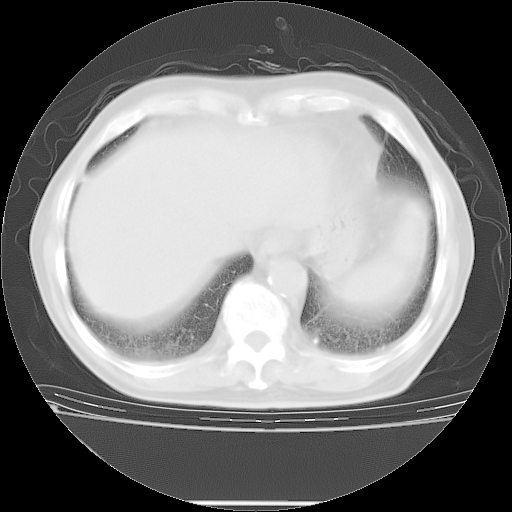

今天复查肺部CT,发现双肺广泛磨玻璃样改变。所以我把3月19日和5月9日相隔50天的肺部CT上传。请大家会诊。

2009年3月19日肺部CT片。

5月9日肺部CT(在4月27日齐鲁医院肺部CT描述部分肺组织磨玻璃样改变,12天后肺组织广泛磨玻璃样改变)